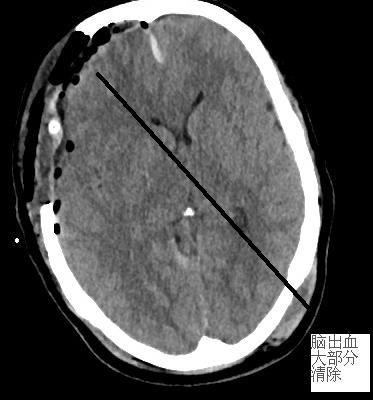

▲上圖為手術(shù)后原血腫位置,血腫已基本清除。

手術(shù)后復(fù)查CT,發(fā)現(xiàn)沈女士手術(shù)區(qū)域血腫基本清除,腦干受壓緩解,生命征平穩(wěn),轉(zhuǎn)病房作進(jìn)一步后續(xù)術(shù)后及康復(fù)治療。